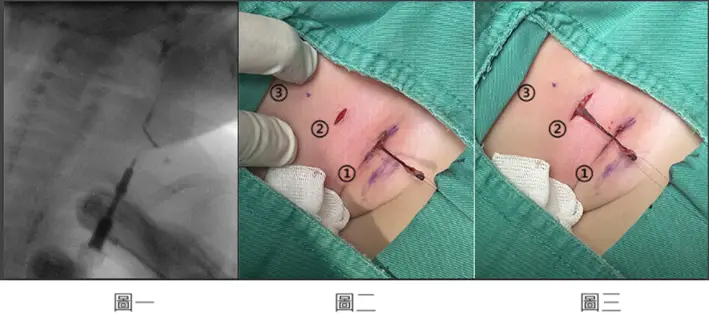

附圖為兒童左頸部瘻管之顯影劑攝影(如圖一)和手術切口實際圖示(如圖二、圖三)。下方傷口為瘻管開口所在位置(如圖中①),上方傷口(如圖中②)靠近下頷(mandible)(如圖中③)。瘻管由下方傷口分離後(如圖二),移轉至上方傷口繼續向上分離後再進行結紮(如圖三)。下列何者最符合本病患之疾病?

圖一(顯影劑攝影 / sinogram)

- X 光顯影劑攝影可見顯影劑沿頸部軟組織向上延伸,呈現線狀瘻管路徑,走行於左頸部,管道由下方開口(外開口)向上延伸。

- 此種攝影可協助判斷瘻管走行方向及內開口位置。

圖二(第一術口分離)

- 手術術野可見三個標記點:① 為下方傷口(瘻管外開口),② 為上方傷口,③ 為接近下頷骨(mandible)的位置。

- 術者由①下方開口開始分離瘻管,瘻管整體由下往上走行,上端靠近下頷骨。

圖三(移轉至上方傷口繼續分離)

- 瘻管由下方傷口分離後移轉至上方傷口繼續向上分離,最終在上方結紮。

- 此「階梯式兩切口技術(stepladder two-incision technique)」為第二對鰓裂瘻管手術的標準術式;然而,上方切口靠近下頷骨(mandible),位置偏高,亦與第一對鰓裂瘻管(1st branchial fistula)的解剖相符,故造成題目爭議。